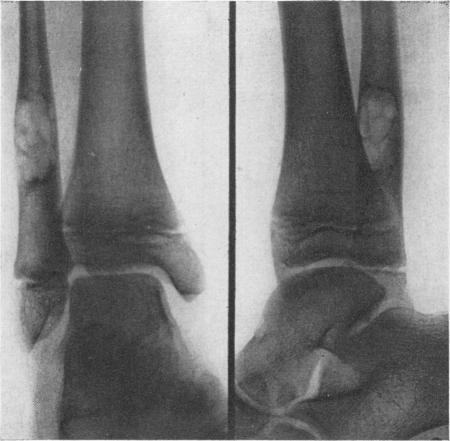

Hatcher C H

Ann Surg. 1945 Dec;122(6):1016-30.